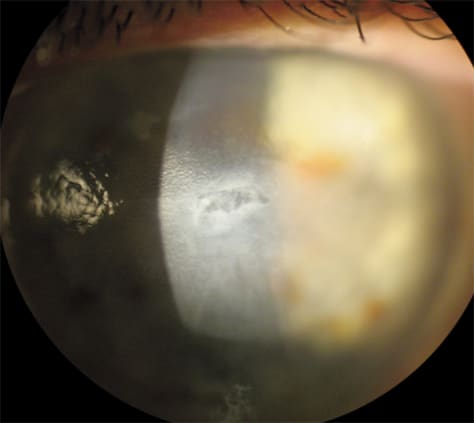

Bullous keratopathy: Bullous keratopathy is characterized by painful eruptions of the corneal epithelial surface that result from long-standing and severe corneal edema secondary to Fuch's corneal dystrophy or postoperative complications that damage the endothelium. A soft contact lens is a perfect bandage to help relieve the patient's symptoms during the acute phase. Fit the patient in a silicone hydrogel lens that has 0.25 mm to 0.5 mm of movement. The contact lens protects the cornea from exposure, which significantly reduces pain (Figure 1). Have the patient wear the lens on an extended-wear basis, and replace lenses as directed by FDA guidelines. These patients may have to wear the lenses on a continuous basis; otherwise the only other course is corneal transplant.

Figure 1. A soft contact lens is the perfect bandage to help relieve symptoms during the acute phase of bullous keratopathy, because the lens protects the eye from exposure, which reduces pain.